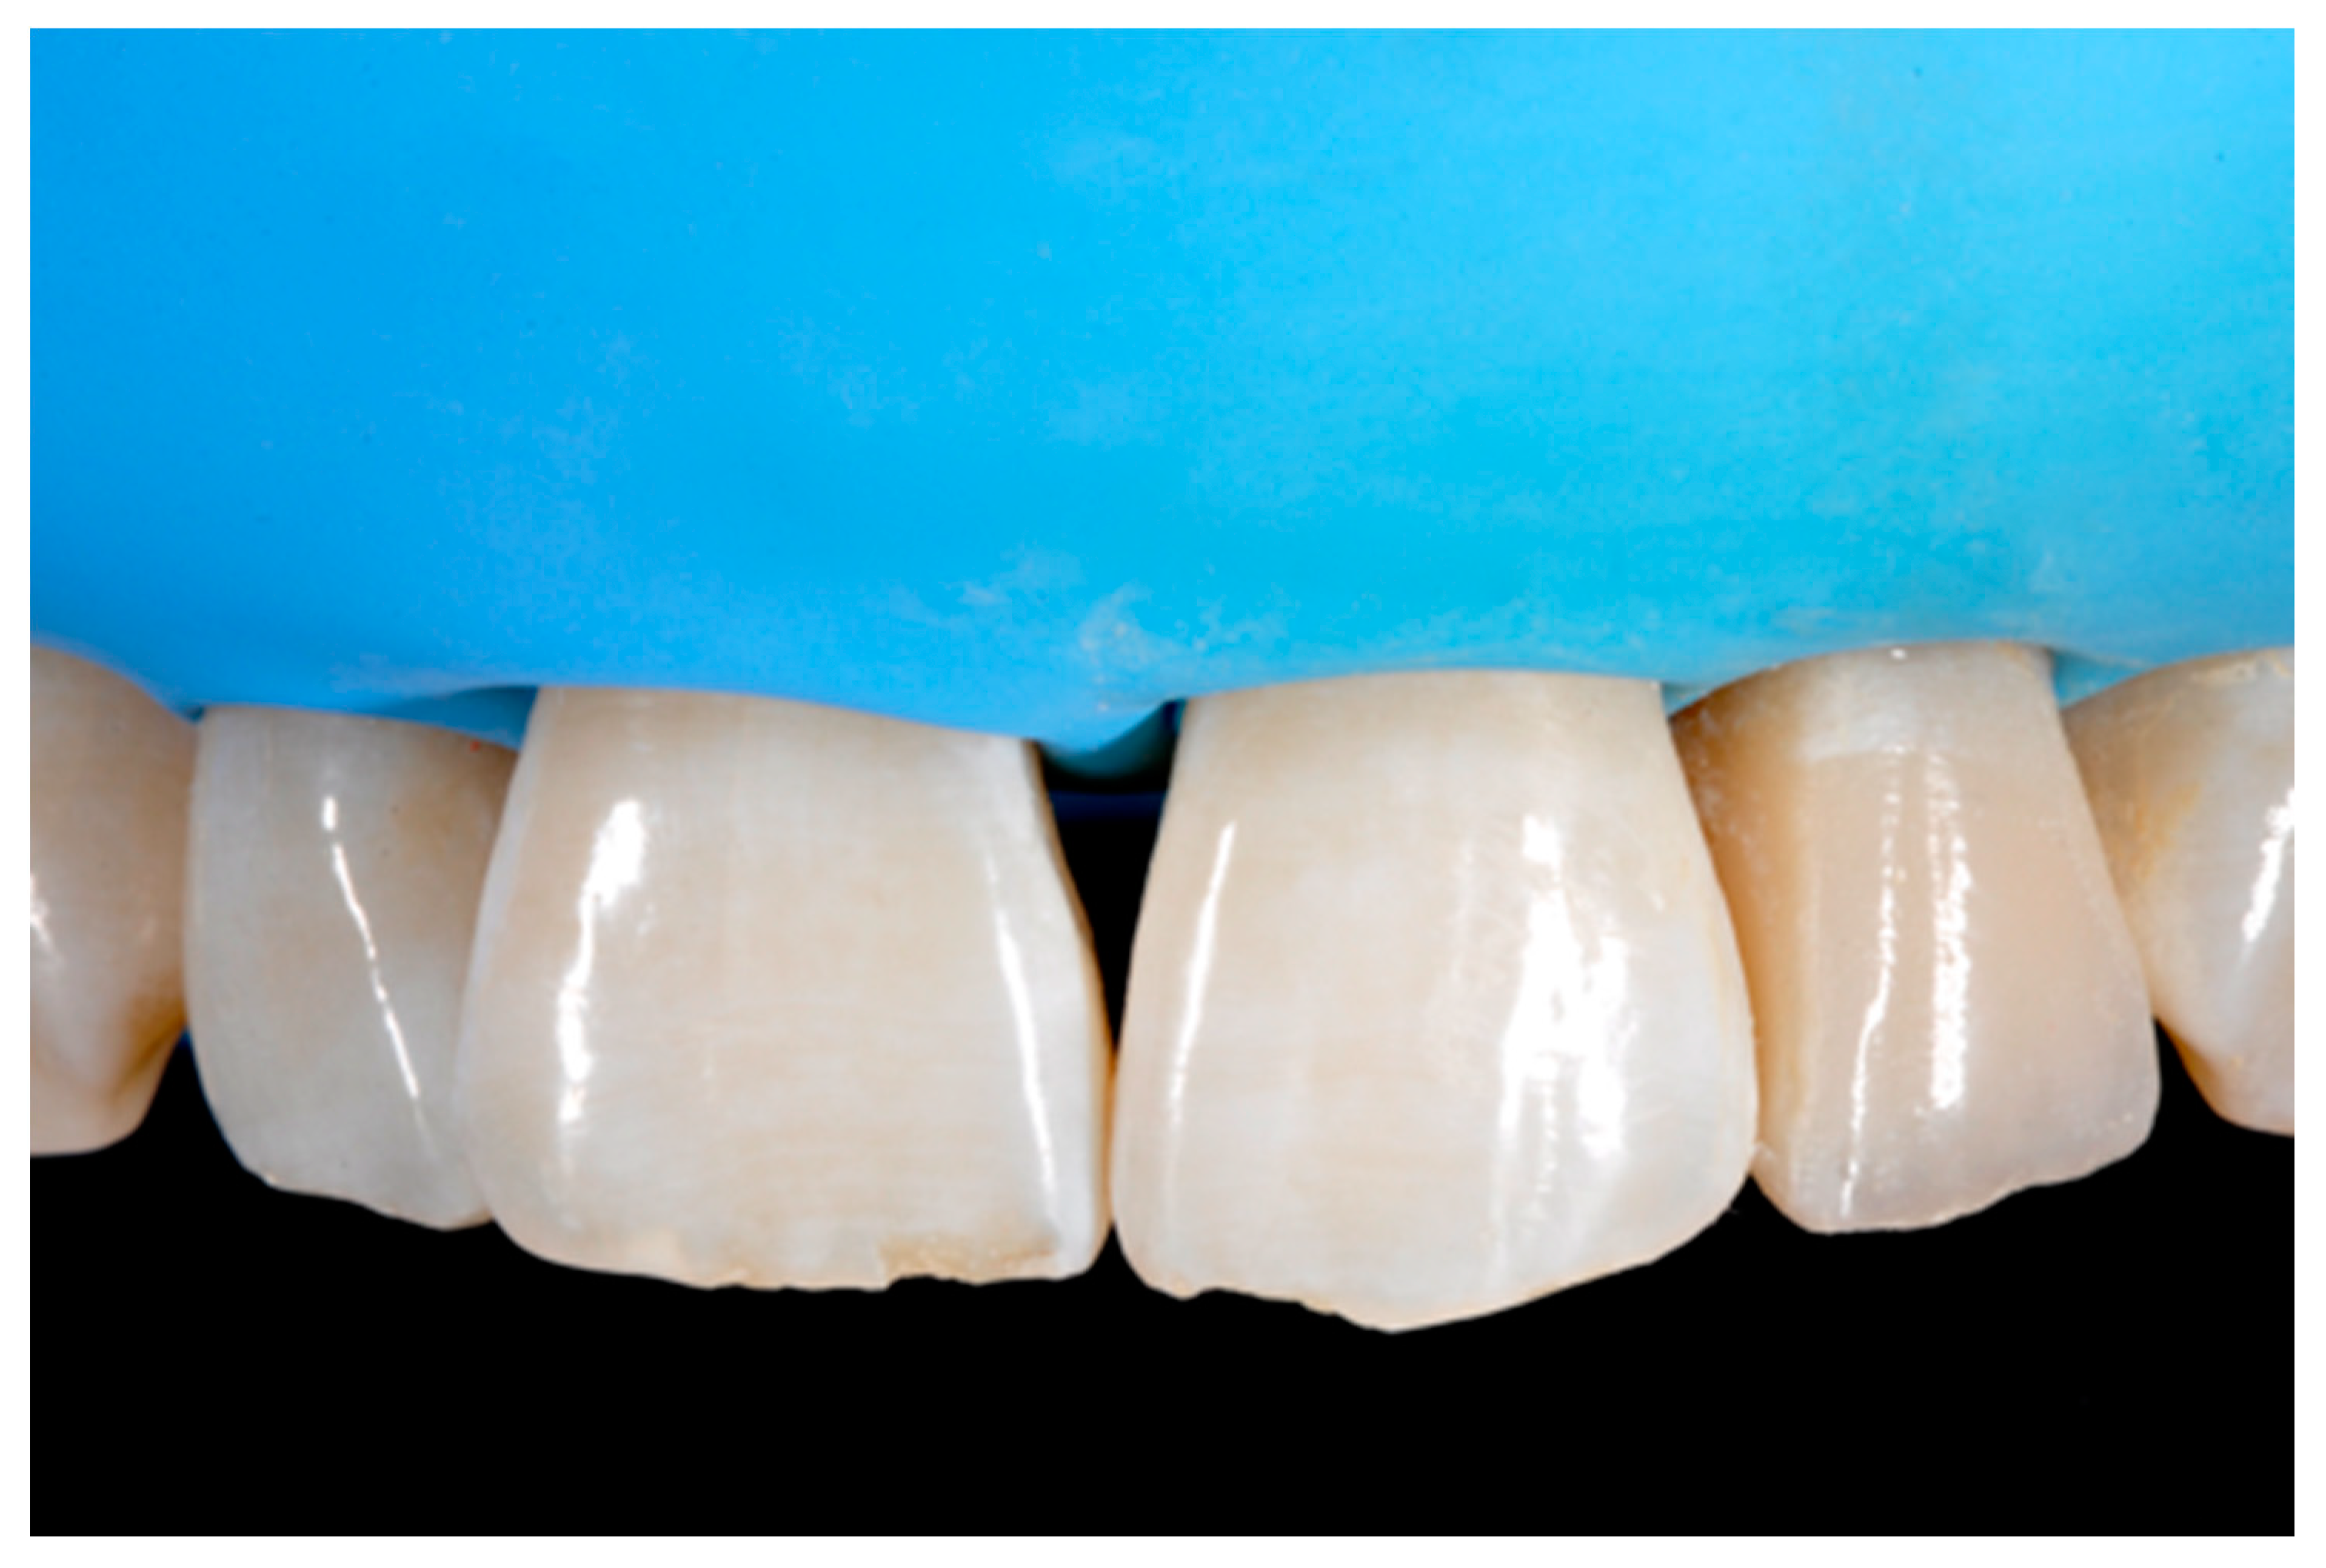

Finishing and polishing procedures were performed with a diamond bur (WL 268 014 Horico, Berlin, Germany), silicone points (Identoflex, Kerr, Bioggio, Switzerland) brushes (Jiffy Goat Air Brushes, Ultradent Products, South Jordan, UT, USA), and diamond pastes (Diamond Polish Mint, Ultradent Products, South Jordan, UT, USA) (Figure 13 and Figure 14). Satisfactory clinical and radiographic outcome was considered satisfactory at 3-months, 1-year, and 5-years post-operative (Figure 15, Figure 16, Figure 17, Figure 18 and Figure 19).

Figure 15.

Three months post-operative. Reprinted from Restauri diretti nei settori anteriori, G. Paolone, S. Scolavino, © 2021, with permission from Quintessence Publishing Italy.